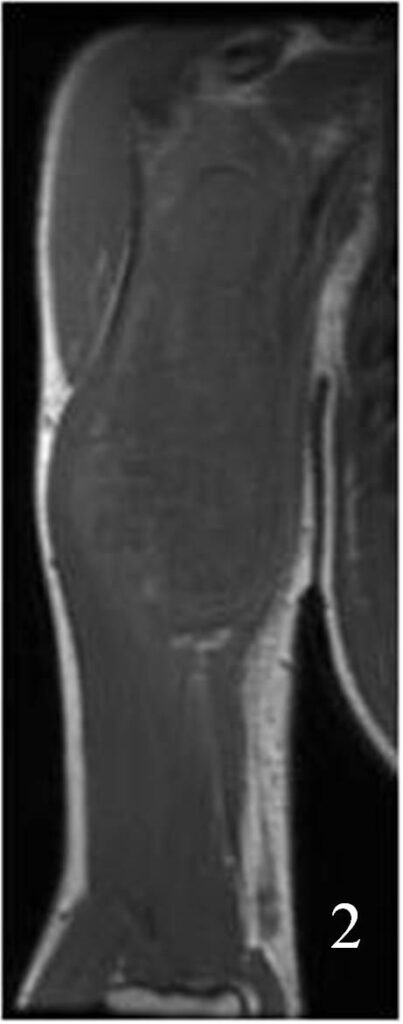

• Intermediate signal isointense to skeletal muscle on T1W (Fig. 1-4)

Fig. 2

Fig. 1-2: Axial (Fig. 1) and coronal (Fig. 2) MRI T1W of an angiosarcoma of the arm shows a well circumscribed heterogeneous lesion. Note the high signal in the center of the mass due to hemorrhage.